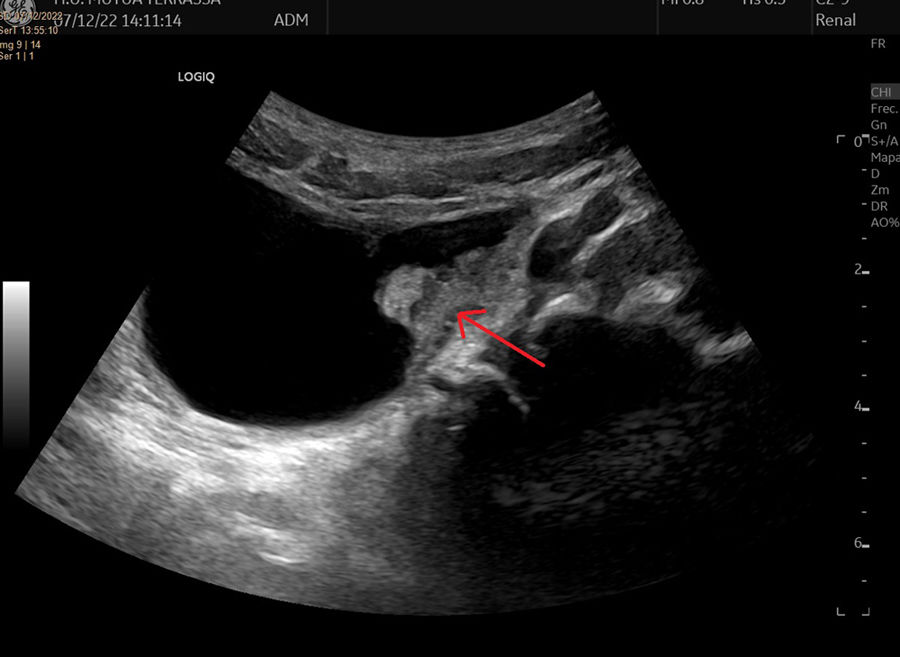

Presentamos el caso de un paciente de 6 años con el hallazgo incidental de un tumor intravesical en una ecografía de control realizada 5 años después de una cirugía de reimplante por reflujo vesicoureteral. La figura 1 muestra la imagen ecográfica, lesión parietal de 10×5mm, de mayor ecogenicidad, márgenes bien definidos y con vascularización en el estudio doppler color. Se evidenció una segunda lesión de similares características. En la cistoscopia se encontraron y resecaron mediante diatermia 4 lesiones, las 2 mencionadas en la ecografía en la cara izquierda y la cara posterior vesical y otras 2 de menor tamaño en la cúpula. La figura 2 muestra la mayor de ellas en la cara lateral izquierda. El diagnóstico histopatológico final fue adenoma nefrogénico de vejiga. La figura 3 muestra las imágenes con tinción de hematoxilina-eosina y el estudio inmunohistoquímico. El paciente se encuentra asintomático y sin recidiva un año después de la intervención. En ocasiones, en el seguimiento rutinario del paciente urológico pediátrico nos encontramos con hallazgos inesperados y es importante conocer entidades poco frecuentes que deben tenerse en cuenta en el diagnóstico diferencial. El adenoma nefrogénico es una metaplasia del urotelio que puede afectar al tracto urinario a cualquier nivel1. Es de naturaleza benigna y se cree que está relacionado con procesos inflamatorios locales o traumatismos repetitivos2. Puede ser asintomático o manifestarse como disuria, hematuria o infecciones del tracto urinario de repetición. El tratamiento de elección es la resección endoscópica completa y es preciso mantener un seguimiento para detectar recidivas3.